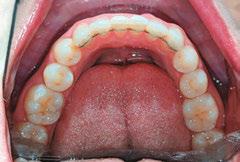

Patient J, a 39-year-old female, (Figures 1, 2, 3, 4, 5, 6) came to the office with concerns about difficulties chewing food and experiencing dry mouth upon waking up in the morning. Additionally, her partner was disturbed by her snoring. Upon examination, several issues came to light:

1. An open bite in the anterior region and a posterior crossbite

2. Breathing through the nose 10% of the time.

3. Lips and cheek muscles actively helping with swallowing food and drinks

4. Lips open 100% of the time

5. Tongue cannot maintain position on a spot, moves between teeth upon swallowing

6. Tongue thrust

7. Weak control over soft palate

Muscle tension around the temporomandibular joint (TMJ) was also evident5 as well as mandibular bilateral lingual torus as response to constant occlusal pressure applied during bruxism.

Figures 5 and 6: 5. Upper arch before treatment. 6. Lower arch before treatment